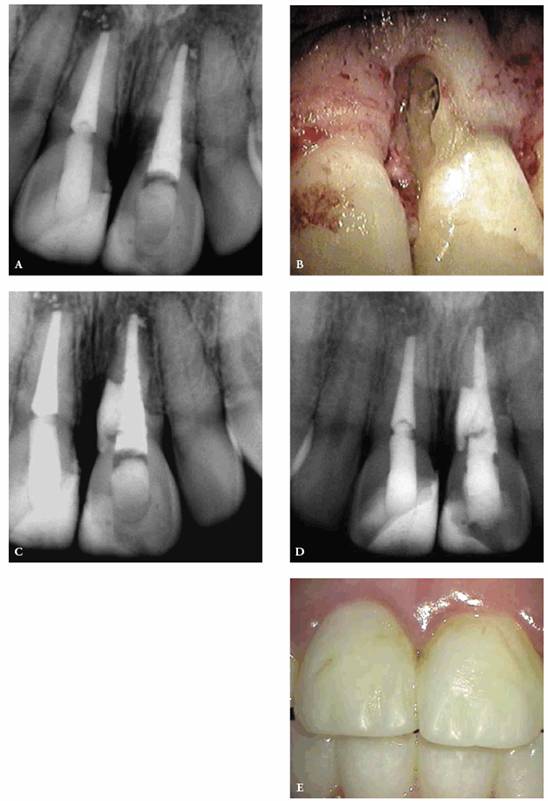

detecting color shifts in a crown (Figures 19-1A, and 19-1B). A tooth with a pink or reddish

hue would more than likely indicate internal hemorrhage from a recent injury (Figure 19-2), a dental procedure (Figure 19-3), or gingival tissue hyperplasia

that has invaded a coronal cavity produced by caries or resorption (Figures 19-4A 19-4B 19-4C, and 19-4D).

Figure 19-4A: Pink spot as a result of external resorption.

Figure 19-4B: Radiograph of the same tooth showing external resorption.

Figure 19-4C: Pink spot as a result of internal resorption.

Figure 19-4D: Radiograph of the same tooth showing internal resorption.

Figure 19-5: Discolored maxillary central incisors with necrotic pulps.

Figure 19-6A: Discoloration from silver-containing root canal cement.

Figure 19-6B: Gray color of crown from a post.

Figure 19-6C: Same radiograph as 19-6B. An unnecessary post that caused the discoloration.

Figure 19-7A: The crown of this maxillary central incisor discolored gradually over a 3-year period following a concussion injury. The complete fill-in of the pulp chamber with dentin is the cause of the yellowish brown hue. In the absence of periapical radiographic changes and clinical symptoms, endodontic therapy is not indicated.

Figure 19-7B: Radiograph of a similar maxillary central incisor 10 years after a concussion injury. The pulp chamber is filled in with dentin producing the discoloration. In this case, there was pulp death years after the discoloration appeared. Because the pulp canal was obliterated, a surgical approach was used to seal the apex.